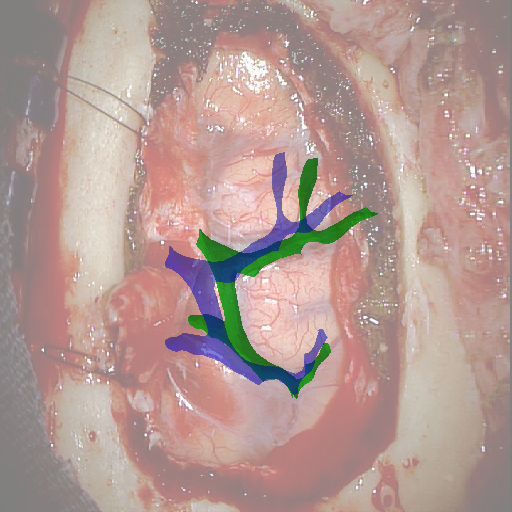

We tested our method retrospectively on 6 clinical datasets from 6 patients (cases) (see Fig. 5). These consisted of preoperative T1 contrast MRI scans and intraoperative images of the brain surface after dura opening. Cortical vessels around the tumors were segmented and triangulated to generate 3D meshes using 3D Slicer. We generated 100 poses for each 3D mesh (i.e.: each case) and used a total of 15 unique textures from human brain surfaces (different from our 6 clinical datasets) for synthesis using . In order to account for potential intraoperative brain deformations [4] we augment the textured projection with elastic deformation [21] resulting in approximately 1500 images per case. The surgical images of the brain (left image of the stereoscopic camera) were acquired with a Carl Zeiss surgical microscope. The ground-truth poses were obtained by manually aligning the 3D meshes on their corresponding images.

Test and Comparison on Clinical Images

We compared our method (Ours) with segmentation-based methods (ProbSEG) and (BinSEG) [7]. These methods use learning-based models to extract binary images and probability maps of cortical vessels to drive the registration. We report in Tab. 1 the distances between the ground truth and estimated poses. Our method outperformed ProbSEG and BinSEG with an average ADD error of mm compared to mm and mm, respectively. Our errors remain below clinically measured neuronavigation errors reported in [4], in which a mm average initial registration error was measured in 15 craniotomy cases using intraoperative ultrasound. Our method outperformed ProbSEG in 5 cases out of 6 and BinSEG in all cases and remained within the clinically measured errors without the need to segment cortical vessels or select landmarks from the intraoperative image. Our method also showed fast intraoperative computation times. It required an average of only milliseconds to predict the pose (tested on research code on a laptop with NVidia GeForce GTX 1070 8GB without any specific optimization), suggesting a potential use for real-time temporal tracking.

Fig. 5 shows our results as Augmented Reality views with bounding boxes and overlaid meshes. Our method produced visually consistent alignments for all 6 clinical cases without the need for initial registration. Because our current method does not account for brain-shift deformation, our method produced some misalignment errors. However, in all cases, our predictions are similar to the ground truth.